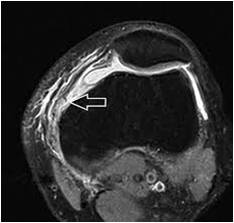

Patella dislocation – MPFL tear

By Sujit Jos | Published November 24, 2022 | Full size is 234 × 223 pixels